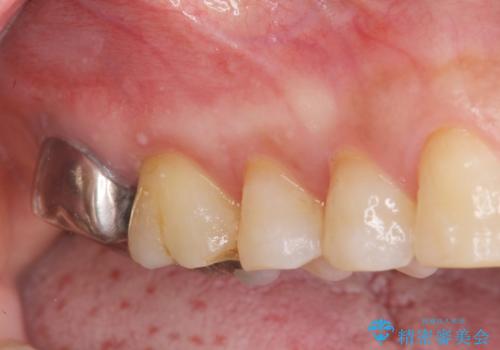

[歯周病治療] 歯周補綴 インプラント補綴

![[歯周病治療] 歯周補綴 インプラント補綴の症例 治療前](https://seimitsushinbi.jp/wp/wp-content/uploads/2020/03/067ed603e15bc4c623e950ffbd6c0829-500x350.jpg?v=1585493851)

![[歯周病治療] 歯周補綴 インプラント補綴の症例 治療後](https://seimitsushinbi.jp/wp/wp-content/uploads/2020/03/93a1bf8bd8e0f11621dbb40f6f1d795c-500x350.jpg?v=1585494318)